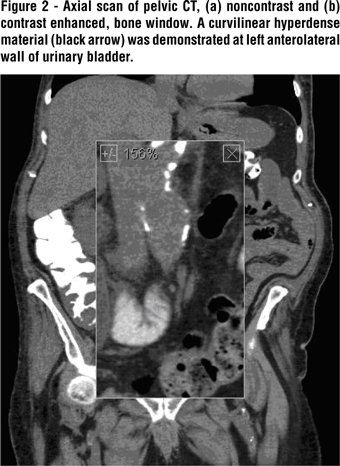

A three-phase contrast-enhanced CT (with intravenous contrast medium reduced to 60 mL, because of elevated creatinine) was performed with both coronal and sagittal reconstructions. An axial slice showed a hugely dilated left ureter with an air fluid level (Figure-1). A coronal reconstruction ( the area of interest enlarged to156%) demonstrates gas in the fistula to the thickwalled segment of the sigmoid colon as well as at the level of the UPJ (Figure-2). Diverticula are shown in the third portion of the sigmoid colon. An aneurysm of the infra-renal segment of the aorta was noted. Another coronal reconstruction (206% enlargement of area of interest) at a slightly more posterior level shows the entire left ureter dilated by gas (Figure-3). A sagittal reconstruction shows the dilated gas-filled left ureter (Figure-4).